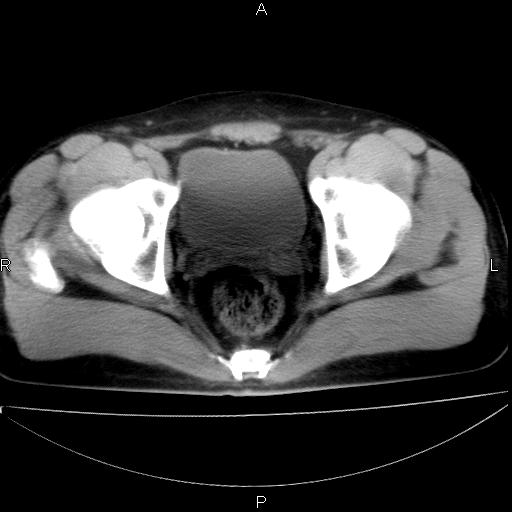

标题: CT29462:双测输尿管扩张

男 25岁 自述 尿频尿急,排尿困难20多天.无腰痛, b超说左肾盂轻度积水,左输尿管上端扩张.未见结石影. ct我看双侧肾盂轻度积水,双输尿管上端都扩张,大家看看能看见结石吗?

考虑肾外肾盂 前列腺轻度肿大 密度欠均 考虑炎性改变

箭头所指不是输尿管,壶腹型肾盂。

肾外肾盂,必要时+c